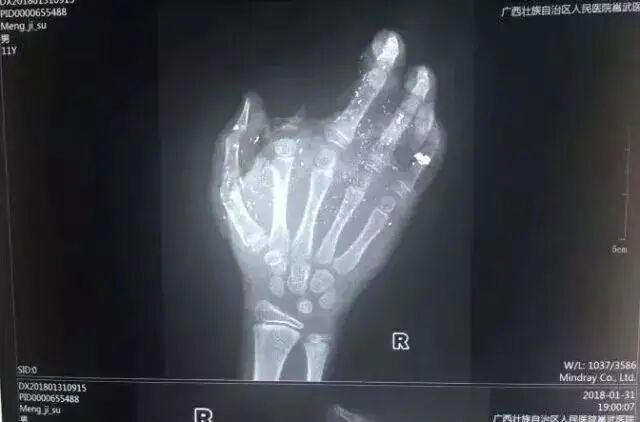

2018年1月31日,广西一小男孩手掌被充电的手机炸得血肉模糊,右手食指被炸没了,拇指、中指、无名指也都炸伤。